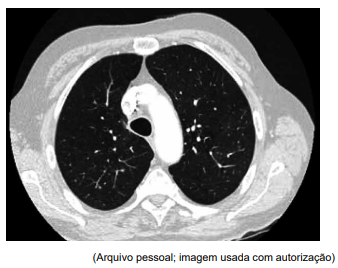

Homem de 76 anos com DPOC é atendido em consulta de rotina. Ele é ex-fumante há quarenta anos e usa terapia inalatória combinada de tiotrópio e olodaterol. Relata piora progressiva da dispneia e aumento do volume de escarro nos últimos seis meses, além de sudorese noturna intermitente e mal-estar geral. Ao exame físico: SatO2 : 94% em ar ambiente; pulmonar com murmúrio vesicular reduzido difusamente. A espirometria mostra (% do previsto): VEF1: 48%; capacidade vital forçada: 81%. Não há achados significativos nos exames de sangue de rotina. Uma de três amostras de escarro coletadas em dias separados é positiva para o complexo Mycobacterium avium. A tomografia de tórax é mostrada a seguir:Homem de 76 anos com DPOC é atendido em consulta de rotina. Ele é ex-fumante há quarenta anos e usa terapia inalatória combinada de tiotrópio e olodaterol. Relata piora progressiva da dispneia e aumento do volume de escarro nos últimos seis meses, além de sudorese noturna intermitente e mal-estar geral. Ao exame físico: SatO2: 94% em ar ambiente; pulmonar com murmúrio vesicular reduzido difusamente. A espirometria mostra (% do previsto): VEF1: 48%; capacidade vital forçada: 81%. Não há achados significativos nos exames de sangue de rotina. Uma de três amostras de escarro coletadas em dias separados é positiva para o complexo Mycobacterium avium. A tomografia de tórax é mostrada a seguir:

Enunciado 4918958-1

Considerando a principal hipótese diagnóstica, o próximo passo mais apropriado no manejo desse paciente é